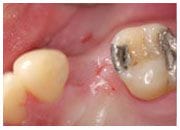

植牙過程

治療前